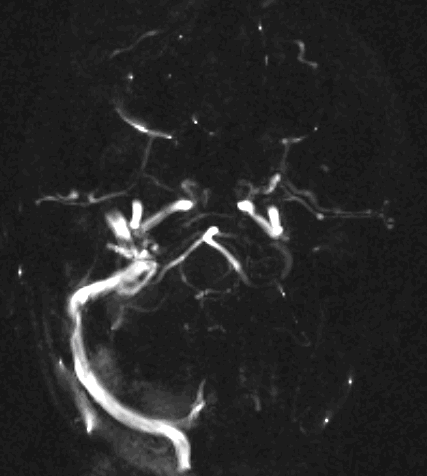

MR angiography (MRA) is an excellent method to visualize brain vessels (arteries, veins, sinuses).

MRA and CTA have completely replaced diagnostic angiography. (Both the sensitivity and the specificity of MRA is greater than 90% in the diagnostics of lesions in the carotid bifurcation.)

Bleeding usually originates from saccular “berry” aneurysms (on the branches of the Circle of Willis). Aneurysm rupture besides subarachnoid hemorrhage can also cause intraparenchymal bleeding when it breaks into the parenchyma.

CT angiography examination is usually advisory in order to confirm the site of the bleeding. It is also effective when a hemorrhagic tumor is in the differentials, although complete differentiation might only be achieved by follow-up examinations. CTA is also essential in the diagnostics of multiple aneurysms (which are prevalent in 20-30% of the cases based on autopsy reports.) In case of a subarachnoid hemorrhage the consequently developing hydrocephalus and its degree might only be detected on follow-up CT examinations. It is very important to note that an initial brain aneurysm rupture might be followed by a second one within the first 7 – 10 days and the resulting vasospasm carries a much higher risk of mortality than the one at the time of the first SAH. This is why the scrutonius review of the acute diagnostic imaging is essential and it plays a fundamental role in patient treatment. Open brain surgery of the aneurysm (clipping) has been replaced by catheter angiography (DSA) nowadays. The aneurysm is either filled up with thrombogenic coils through its neck or recently bypassing stents are inserted to exclude the aneurysm from the cerebral circulation.